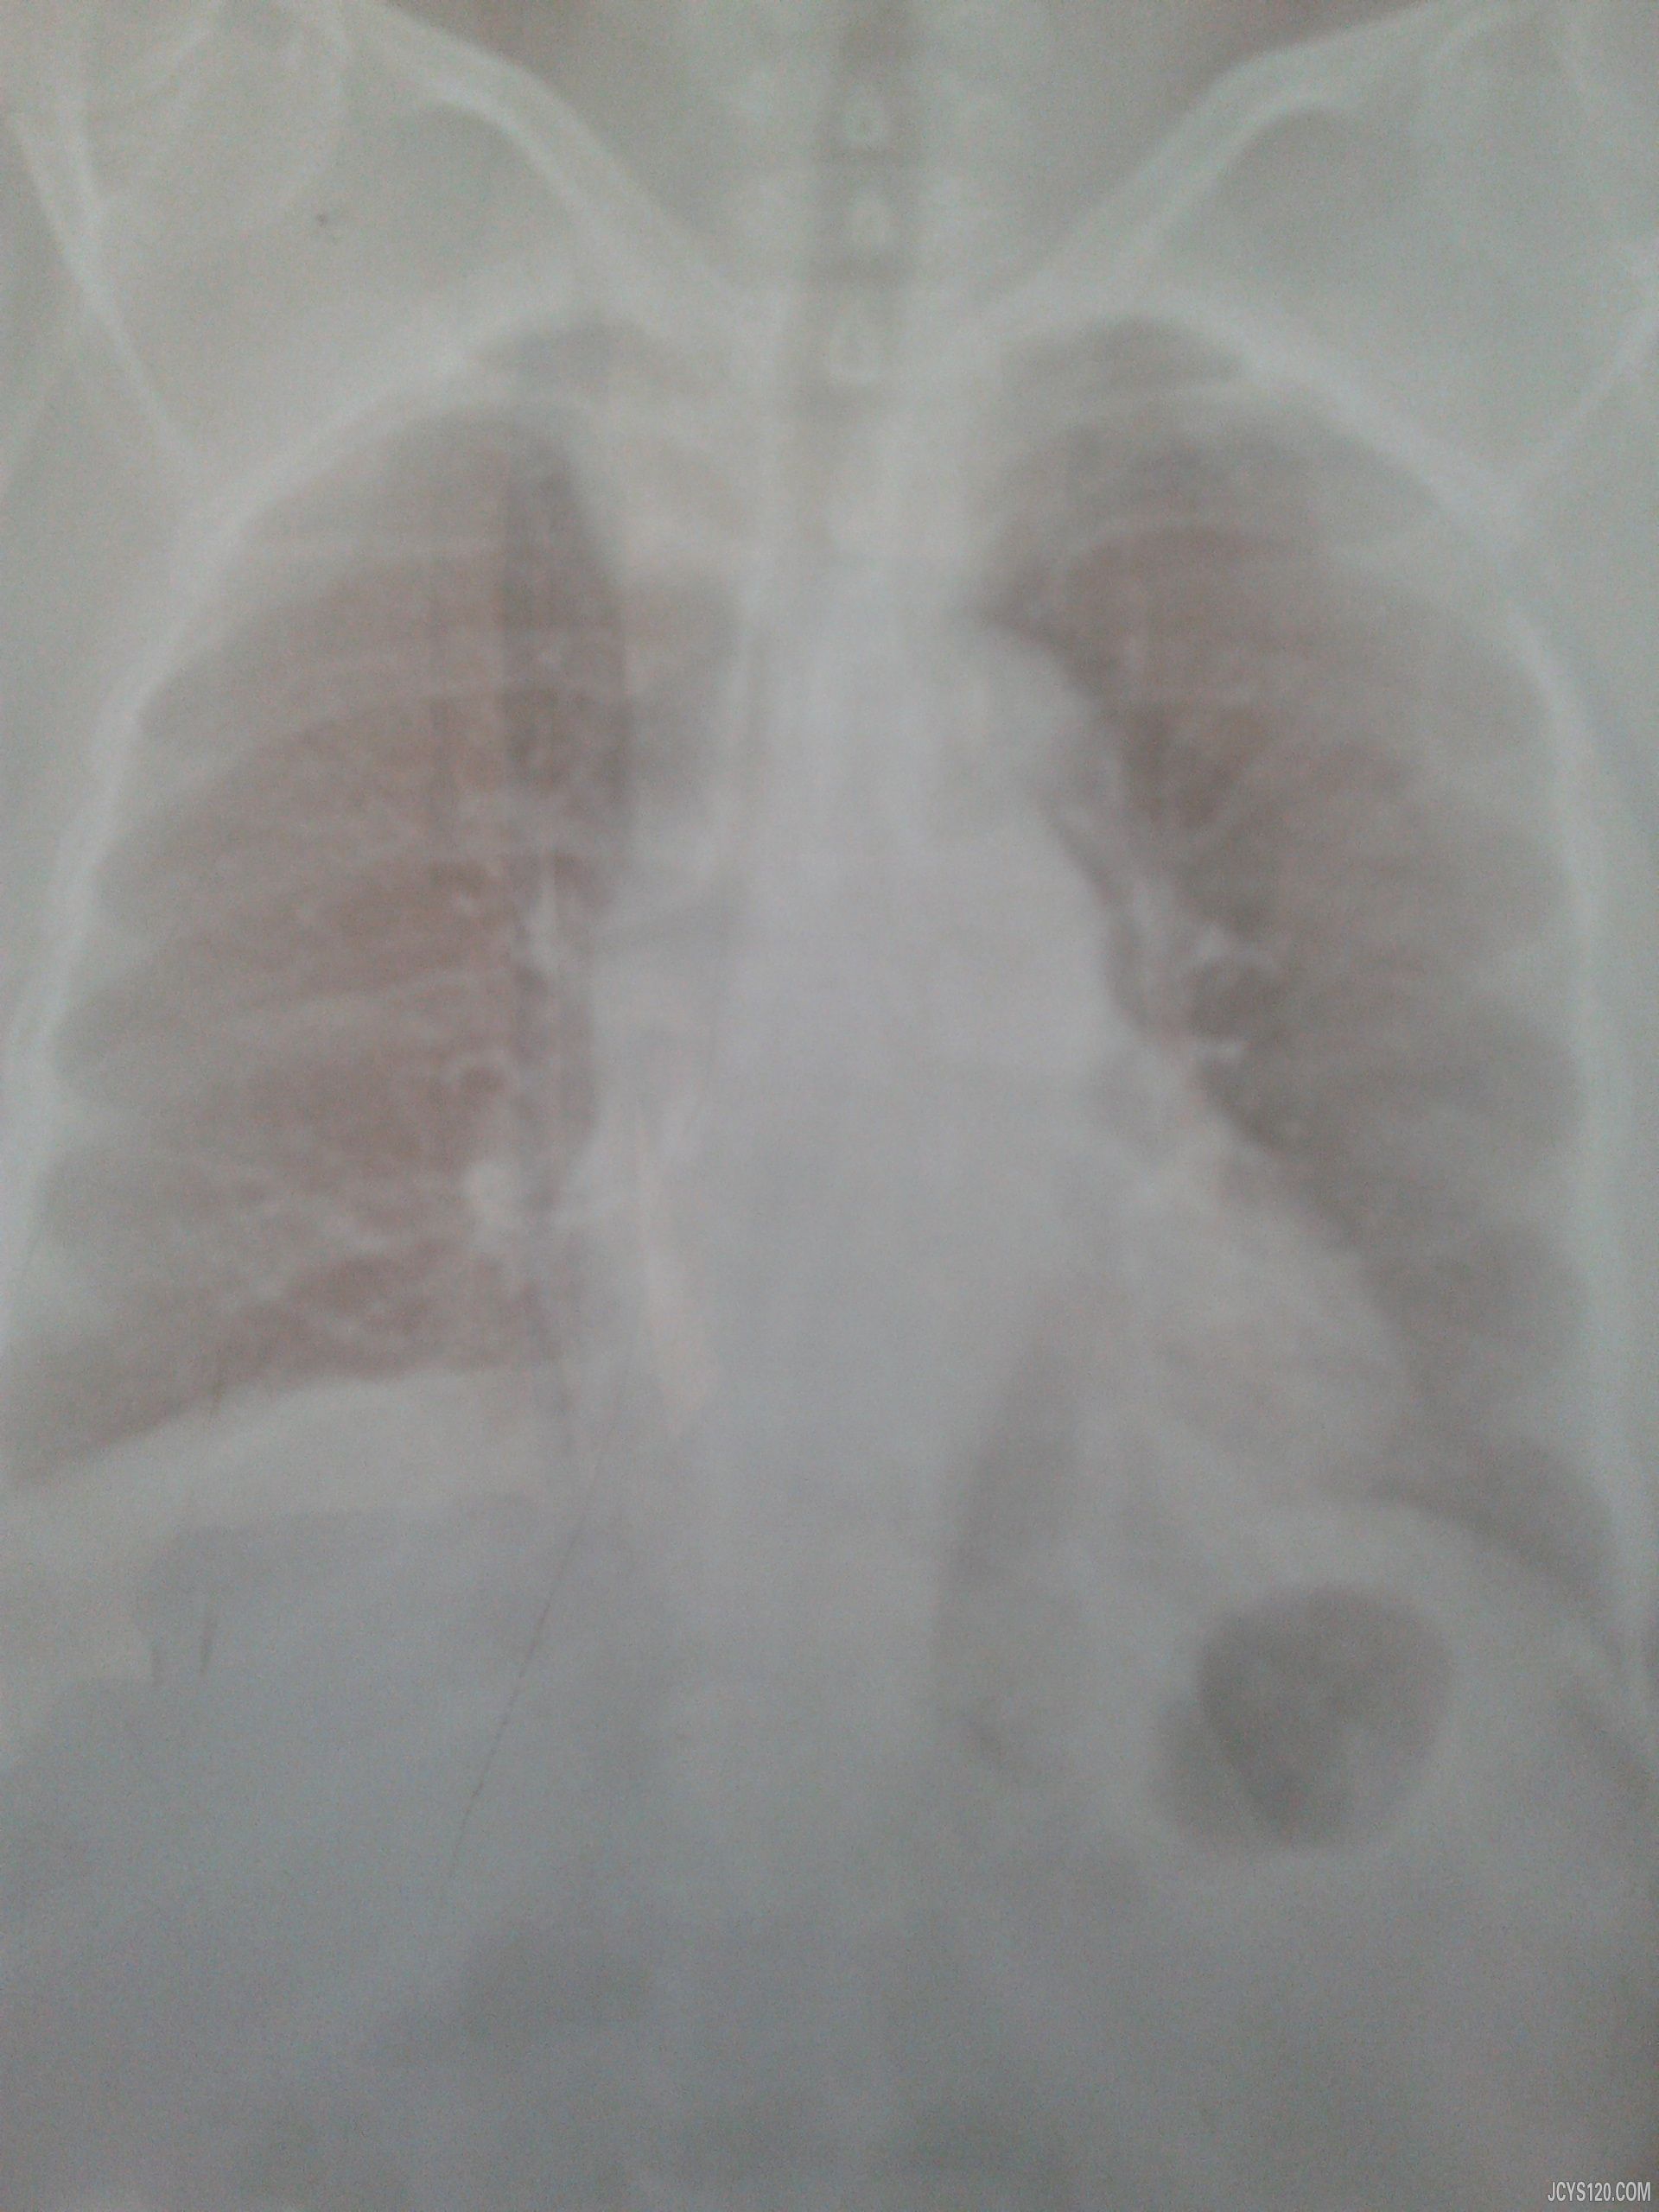

• 左侧胸痛伴呼吸困难10天 attach_img agree

• wjl8742693 2013-4-15

• 患者,男性,48岁,务工, 10天前在无明显诱因下感到少许咳嗽,无痰,不在意。两天后自己觉得左侧胸痛,有肩部和腹部放射牵拉,随着呼吸困难,痰量少许,无血性分泌物,问诊中没有发热,消瘦,盗汗不明显,稍有 ...  阅读全文>